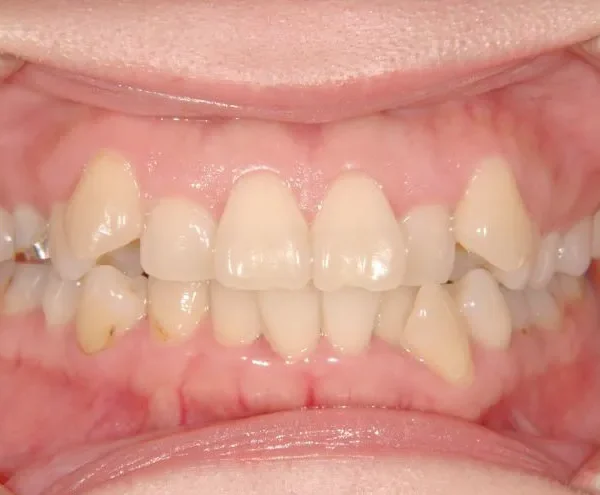

初診時年齢 40歳以上 (女性) 主訴 上下のがたがた・噛み合わない

診断名 叢生 装置名

上下のがたがたと噛み合わない事を主訴に来院されました。

歯は抜かずに矯正治療しました。

治療回数35回、2年8ヶ月の治療期間で矯正治療を終了しました。

噛み合わせが安定する事で、大きくなっていた咬筋が正常な大きさになり、顎のラインもシャープになり大変よろこばれていました。

また今回の症例は、歯科矯正用アンカースクリューを用いた治療の本に掲載されました。